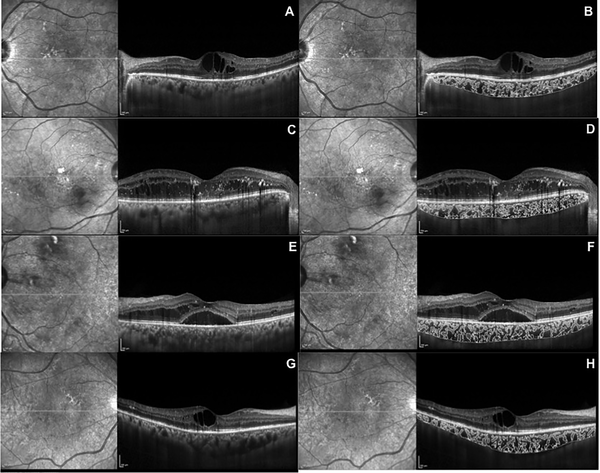

Normal retinal thickness

In a healthy adult eye, the average retinal thickness measured by Optical Coherence Tomography (OCT) is approximately 250–280 micrometers in the central macula, while the peripheral retina is naturally thinner. Any significant reduction from these values is considered abnormal and may indicate retinal thinning.

Early detection of retinal thinning is extremely important because lost retinal tissue cannot be regenerated. Tests such as OCT scans, visual field analysis, and detailed fundus examination help detect thinning at an early stage. Timely management can slow disease progression and preserve remaining vision.